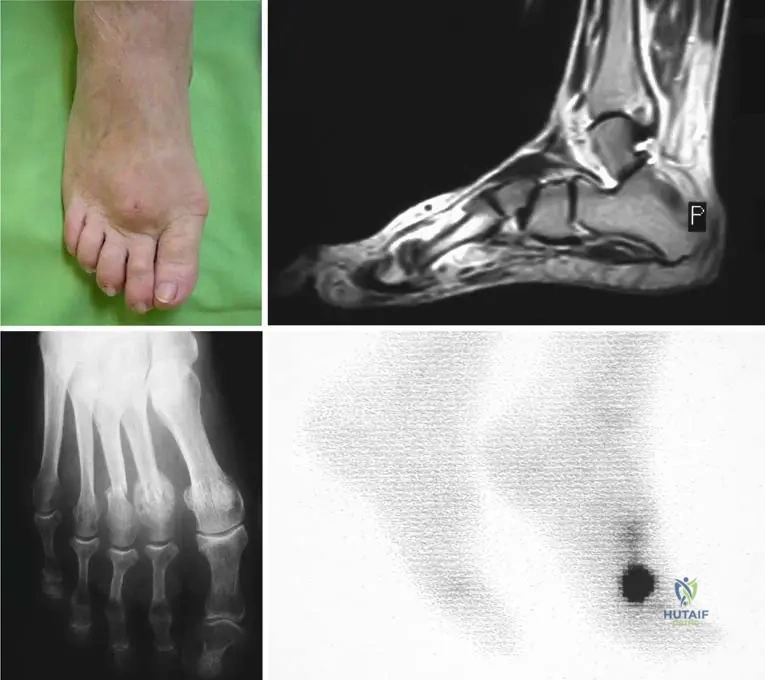

A 24-year-old male presents with chronic leg pain and a waddling gait. Radiographs of his lower extremities are shown. Based on these images, what is the most striking radiographic feature that confirms the diagnosis of Camurati–Engelmann disease?

View Answer & Explanation

Correct Answer: C

Rationale: Fig. 1.120 a–c is captioned: "Diaphyseal cortical thickening and sclerosis of long tubular bones are the main characteristics of Camurati-Engelmann disease." The images clearly illustrate this feature in the humerus, femur, tibia, and fibula. Options A, B, D, and E describe features not seen in the provided images or characteristic of this disease.